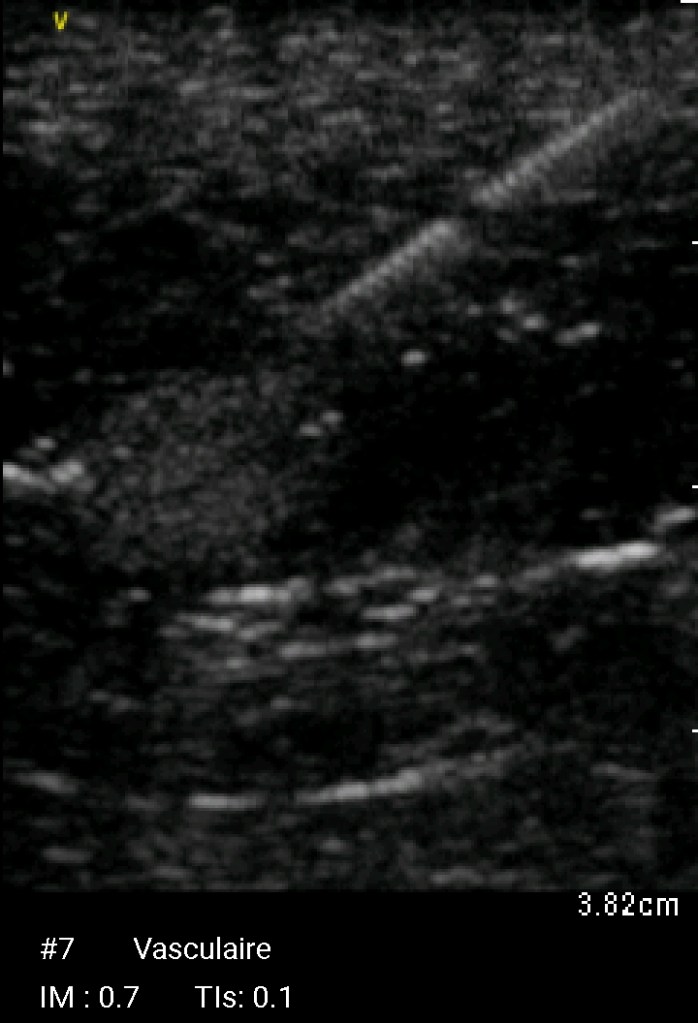

Echographie Sous-clavièreJugulaireFémorale JUGULAIRE G FEMORALE Dt MorissonKohlerDouglas Sous-clavièrePleural J’aime chargement…